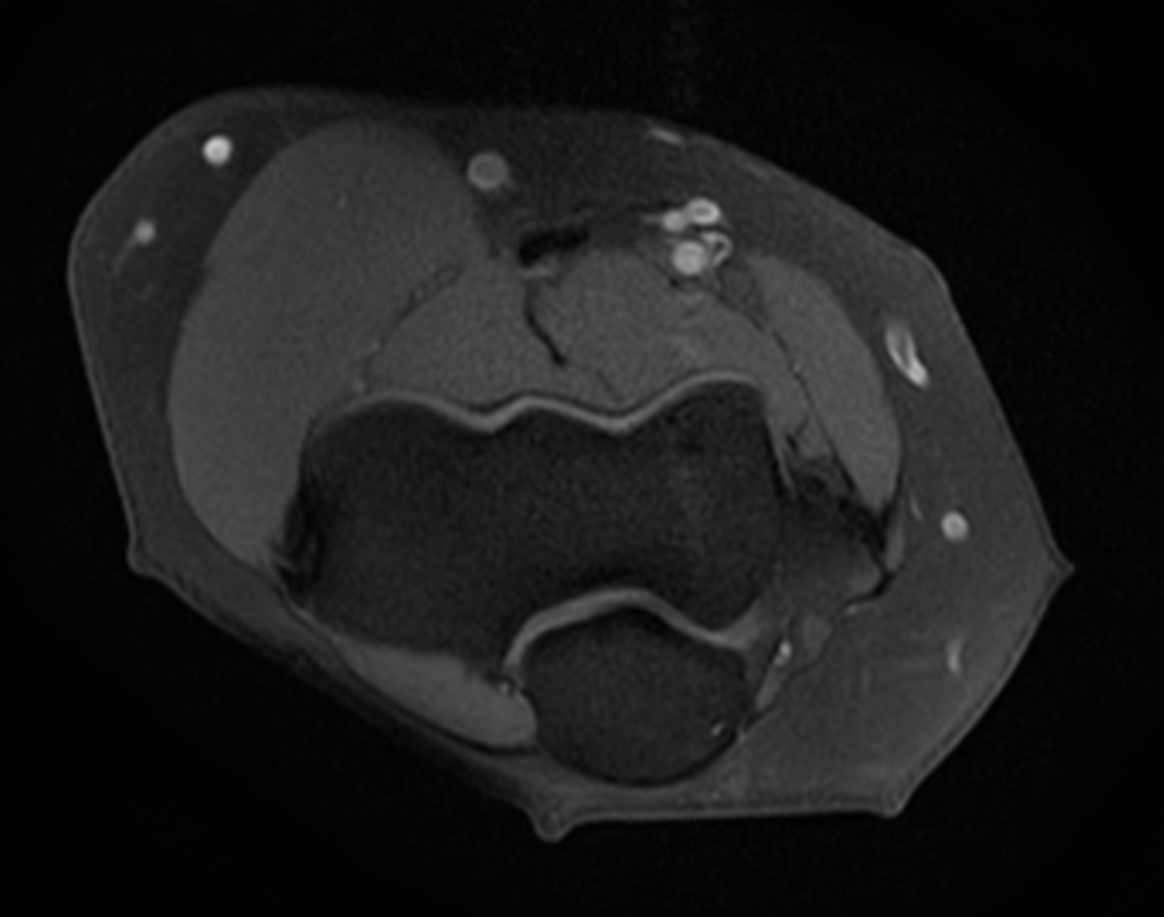

Axial T1w TSE